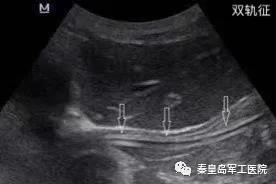

为提高危重症患者置管成功率,王秋艳主任与姚明慧护士长配合,通过床旁超声引导下成功进行鼻肠管的置入。床旁超声被喻为看得见的“听诊器”,在重症医学科的应用日益广泛。该技术利用超声优势,在床旁进行实时引导,准确通过幽门后进行肠内置管。

相比传统方法,超声引导更加安全稳定,无副作用,置管成功率高。通过超声评估胃排空功能,测量胃残余量等优势,可以尽快给足营养支持,更好的保证患者安全,有效节省人力资源。